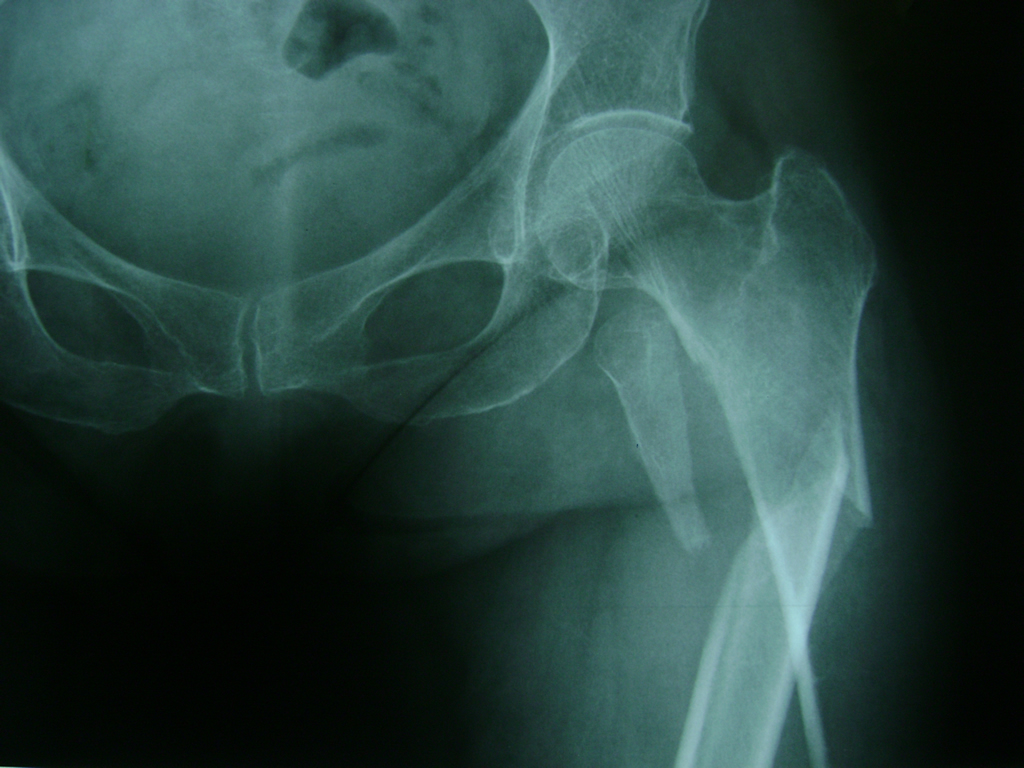

La cirugía de fractura de cadera se realiza para reparar una ruptura en la parte superior del hueso del muslo. Este hueso se denomina fémur.

Es parte de la articulación coxofemoral. Si una fractura de cadera no recibe tratamiento, es posible que deba permanecer en una silla o en la cama.

A menudo se recomienda la cirugía para reparar la fractura debido a dichos riesgos.